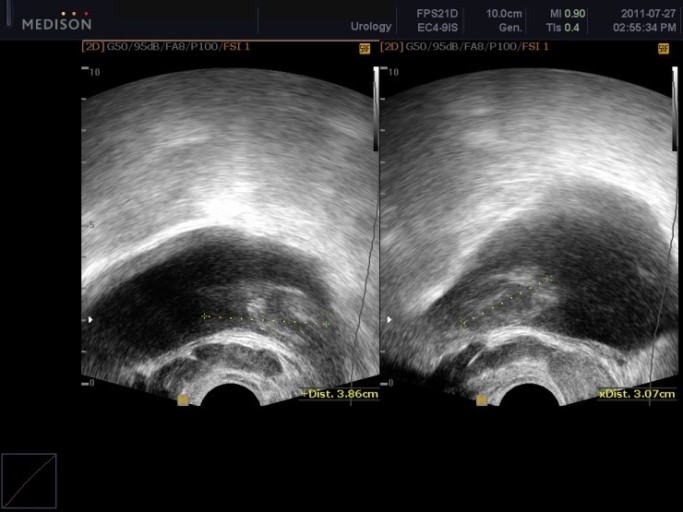

전립선암 초기증상 전립선암 발병 위험이 높은 남자나이나 일정 연령 이상의 남자는 특히나 더 조심해야 하고 항상 신경 써야 해요. 전립선암은 남자의 생식기관에 위치한 작은 샘인 전립선에 발생하는 암의 일종인데요. 전립선은 정자에 영양을 공급하고 지켜주는 체액을 생산하고 분비하는 할 일을 해요. 전립선암은 전립선의 비정상 세포가 성장하고 통제할 수 없이 증식해서 종양을 형성할 때 발생해요.

전립선암은 느리게 성장할 수 있으며 초기 단계에서는 무증상인 그럴 경우가 많아요. 그러나 암이 자라서 전립선을 넘어 전이된다면 배뇨 곤란, 소변 또는 정액의 혈액, 뼈 고통 및 피로와 같은 심각한 고통을 일으킬 수 있어요.